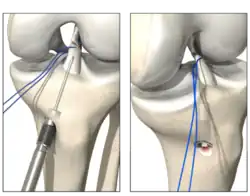

Das gerissene Kreuzband wird mit resorbierbaren Fäden angeschlungen und wieder an die anatomische Stelle am Oberschenkel reponiert. Danach wird eine Schraube mit einem Federsystem im Unterschenkel verankert (Ligamys[3]). Ein Polyethylenfaden wird danach hinter dem genähten Kreuzband ins Kniegelenk gebracht und am Oberschenkelknochen mit einem Plättchen fixiert. Dieser Polyethylenfaden wird anschließend im Federsystem mit 80 Newton vorgespannt und fixiert, so dass das Kniegelenk in jeder Position stabilisiert werden kann. Das genähte Kreuzband erhält somit die notwendige Ruhe und Stabilität zur Heilung. Als letzter Schritt wird an der Abrissstelle im Oberschenkelbereich ein Microfracturing durchgeführt. Dadurch gelangen Stammzellen und Wachstumsfaktoren vom Knochenmark des Oberschenkels in die Risszone des Kreuzbandes und regen die biologische Heilung des Bandes an.